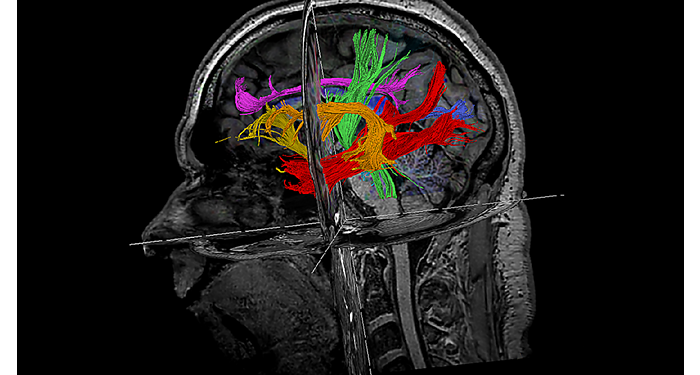

70% of radiologists consider neuro indications to be challenging, mostly due to a lack of appropriate imaging and visualization techniques¹. Philips aims to provide the best possible diagnostic clarity and treatment guidance for all patients with neurological disorders. By leveraging our dStream digital platform, this year, we are introducing, a set of novel imaging and visualization strategies. These may empower you to resolve complex neuro questions with more certainty, as well as unlock new neuro territories in advanced Neurofunctional applications. This is a key step towards elevating neuro diagnostics and ultimately touching more lives with MR imaging. ¹ TMTG Market Survey 2016

New neuro applications